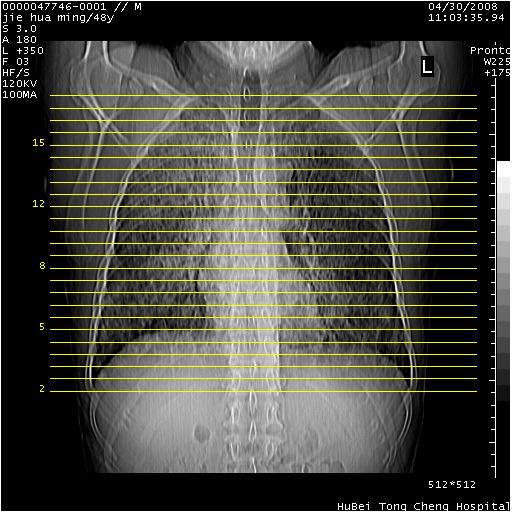

以下是引用dr.yang在2008-5-1 6:25:00的发言:[br]两肺广泛毛玻璃样的片状影,密度不均,边缘欠清,呈碎石路样改变,[br]考虑,1双肺间质性肺炎,2肺泡蛋白沉积症3支气管肺泡癌[br]

以下是引用zsl6918在2008-5-1 7:35:00的发言:[br]双肺磨玻璃样病变,可见铺碎路石征,病变区与正常区交错。边界清晰。符合肺泡蛋白质沉着征,高分辨扫描会更清楚漂亮。建议临床肺泡灌洗。

以下是引用yangyudong333在2008-5-1 5:36:00的发言:[br][br] 两肺广泛毛玻璃样的片状影,密度不均,边缘欠清,呈碎石路样改变,[br]考虑,1双肺间质性肺炎,2肺泡蛋白沉积症[br]